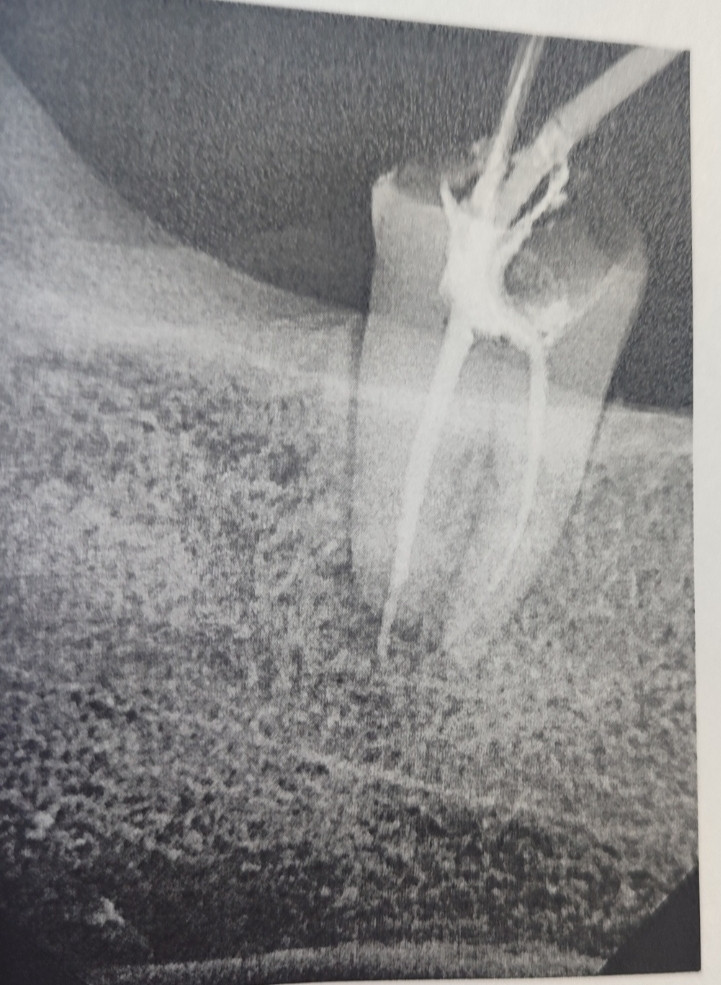

Здравствуйте! По снимку видно лечение каналов, но при сильной боли и такой картине прогноз сомнительный. Сохранить зуб иногда возможно через перелечивание у эндодонтиста, однако в ряде случаев требуется удаление.